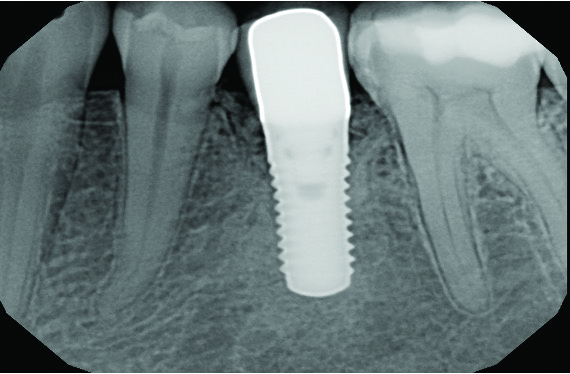

At 5 years post-implant placement, implant site No. 20 showed circumferential depths of 6 mm to 8 mm with heavy bleeding on probing (Figure 1).1,47 The keratinized mucosa width locally recorded 4 mm buccally and lingually, with a thick gingival phenotype. The four-wall intrabony lesion was diagnosed as a class 1c (circumferential) intrabony peri-implant defect with less than 40% defect angulation in the mesial and distal radiographic aspects (Figure 2).48 Additionally, resin cement-associated peri-implantitis was diagnosed.49 The patient preferred to maintain the existing well-fitting crown due to financial concerns. The patient would be considered low-medium risk according to the PIDRA (Table 3). (To view Table 3, the PIDRA for this case, visit compendiumce.com/go/2505.)

Fig 2. A radiograph of the dental implant area before treatment depicted the defect angle, which was less than 40%.

Figure 2